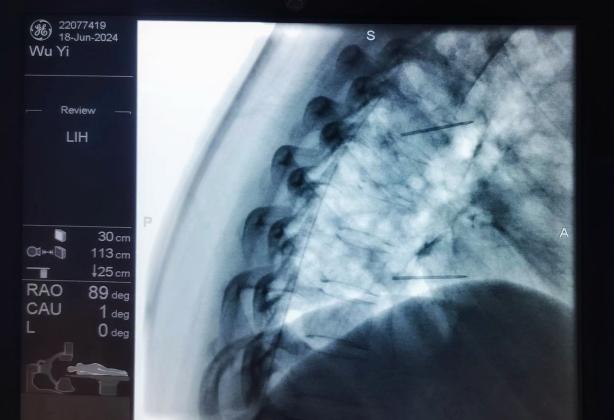

3.癌痛規(guī)范化管理:癌痛是癌癥患者最常見和難以忍受的癥狀之一,不僅嚴(yán)重影響患者的睡眠、飲食,而且加重患者心理負(fù)擔(dān),導(dǎo)致焦慮、抑郁等,嚴(yán)重影響患者的生活質(zhì)量。癌痛的治療方法包括:病因治療、藥物止痛治療和非藥物治療。癌癥患者常面臨難以控制的疼痛,傳統(tǒng)的藥物治療在這些患者中可能效果有限或伴隨嚴(yán)重副作用??剖以阼瞪降貐^(qū)率先采用了鞘內(nèi)藥物輸注(Intrathecal Drug Delivery, IDD)進(jìn)行癌痛管理,通過將藥物直接輸送到脊髓鞘內(nèi),可以顯著提高藥物的局部濃度,從而增強(qiáng)鎮(zhèn)痛效果并減少全身副作用。

鞘內(nèi)泵植入術(shù)